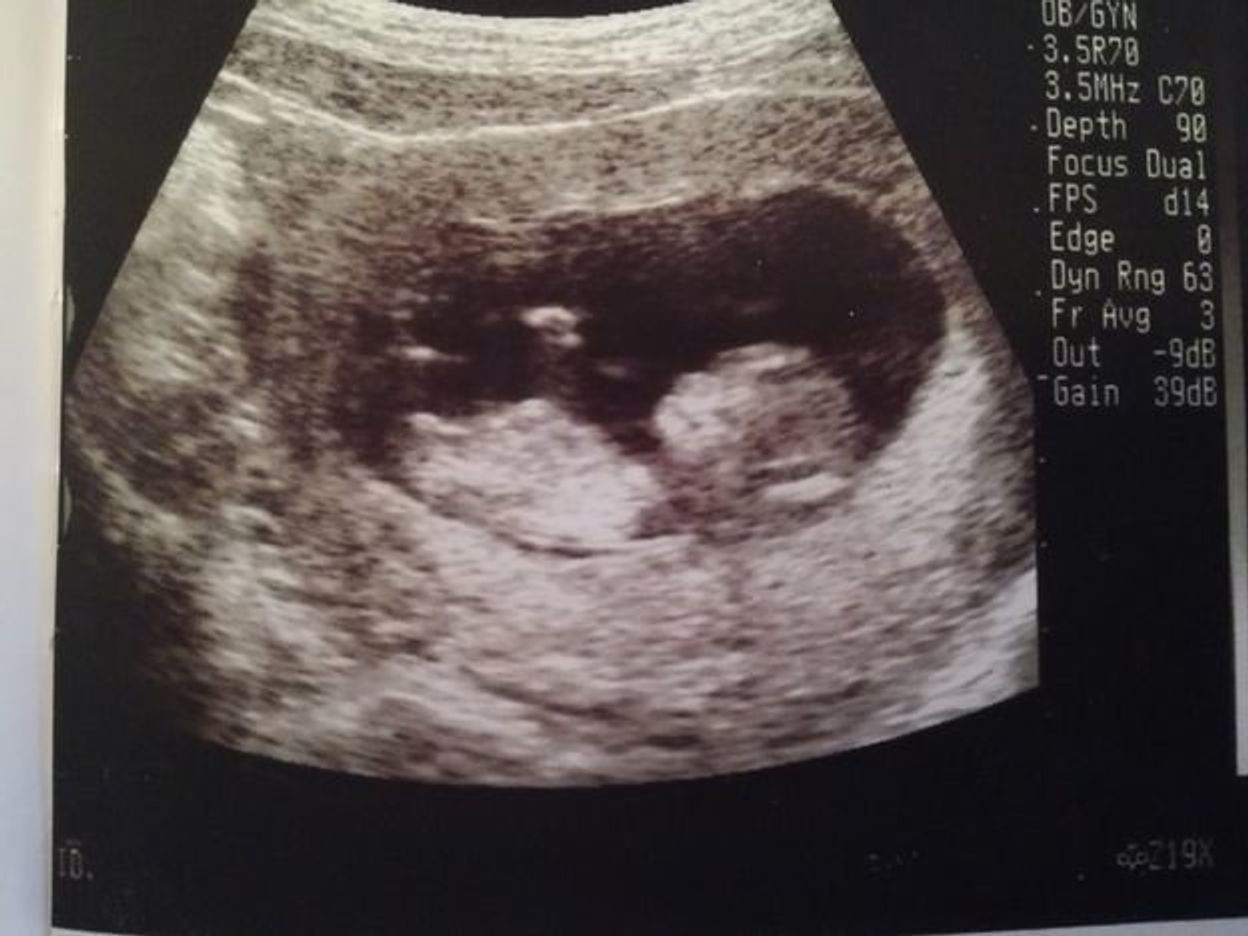

僕の子供はまだお腹の中にいますが少しづつ家庭をお持ちのビジネスマンの気持ちがわかるようになりました。

繰り返しにはなりますが僕はまだ完全に親にはなっておらずお腹の中に命がいる状態です笑

僕の話になりますがパートナーが日々頑張ってお腹の赤ちゃんと向き合っている状態です。